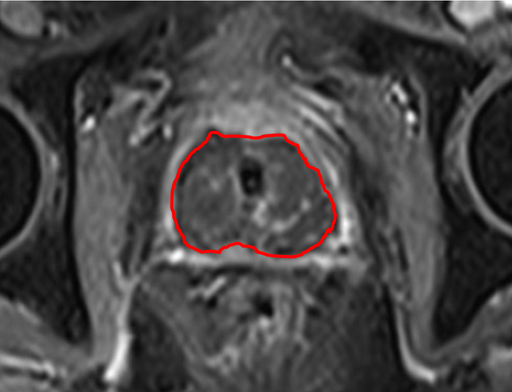

MR images

Image 1 shows the effect of the entire prostate gland treatment of patient 9. The dark area indicates good treatment effect.